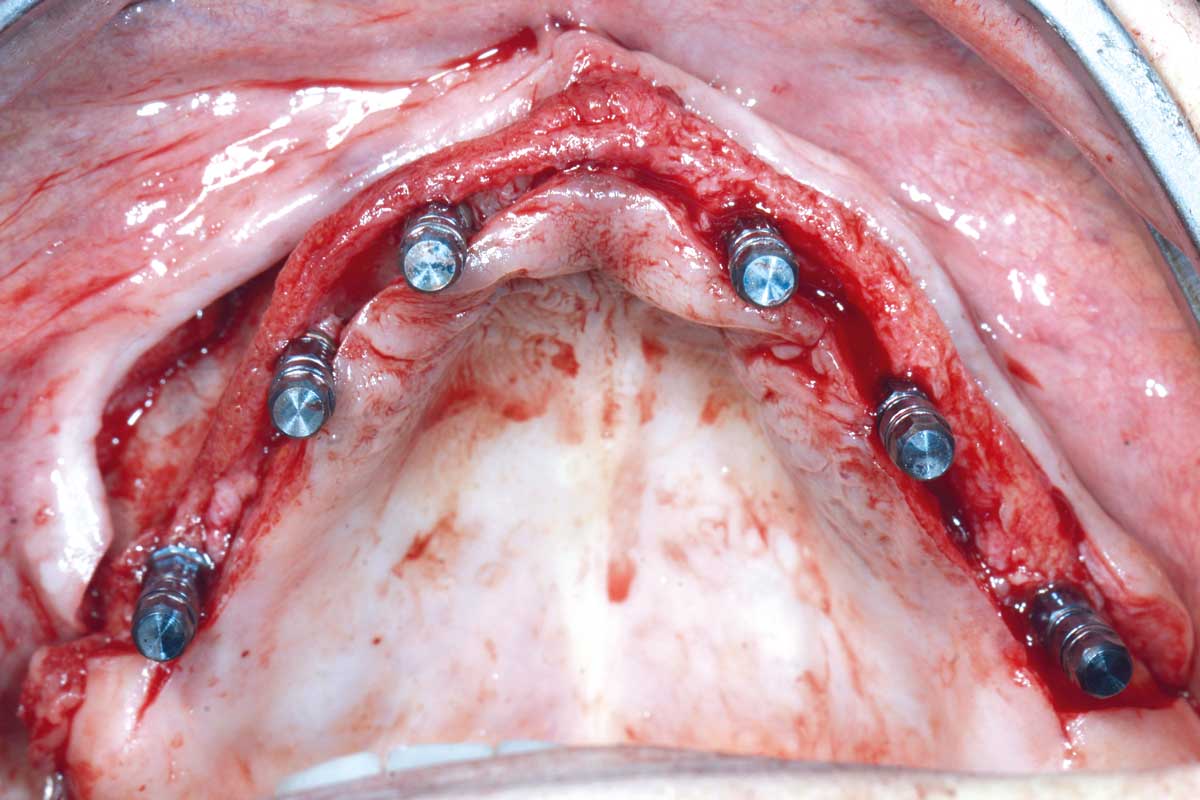

Full arch GBR using cerabone®, maxgraft® and Jason® membrane with simultaneous implantation of 6 Straumann® implants - Dres. A. Signorio and G. Molina